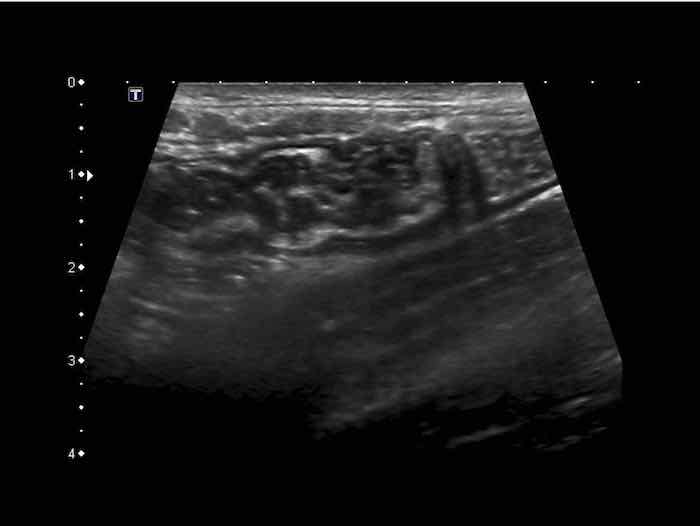

Đây là hình ảnh của hồi tràng tận cùng ở ba trẻ em và người trẻ tuổi khác nhau với các mảng Peyer lớn biểu hiện dưới dạng dày lớp niêm mạc sâu không đối xứng, giảm âm.

Với mỗi kháng nguyên mới, mô bạch huyết lại được tái hoạt hóa.

Ở bệnh nhân trẻ tuổi, cả hạch bạch huyết mạc treo ruột và các mảng Peyer đều lớn hơn nhiều so với người trưởng thành – kể cả về kích thước tuyệt đối.

Mô bạch huyết bị kích thích ở trẻ em không chỉ dẫn đến các mảng Peyer nổi bật ở hồi tràng đoạn cuối và các hạch bạch huyết mạc treo ruột phì đại (hình dưới bên trái), mà còn gây ra tình trạng dày lớp niêm mạc sâu của ruột thừa (hình dưới bên phải).

Lưu ý rằng các phần lồi ra –đôi khi giống polyp- (góc trên bên phải), có thể đóng vai trò là điểm dẫn đầu trong lồng ruột hồi-manh tràng điển hình ở trẻ nhỏ